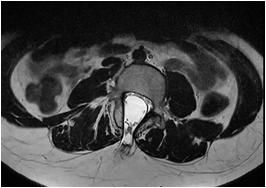

Fig 1 — CT Imaging from a patient of Basal Ganglia hemorrhage in the present study